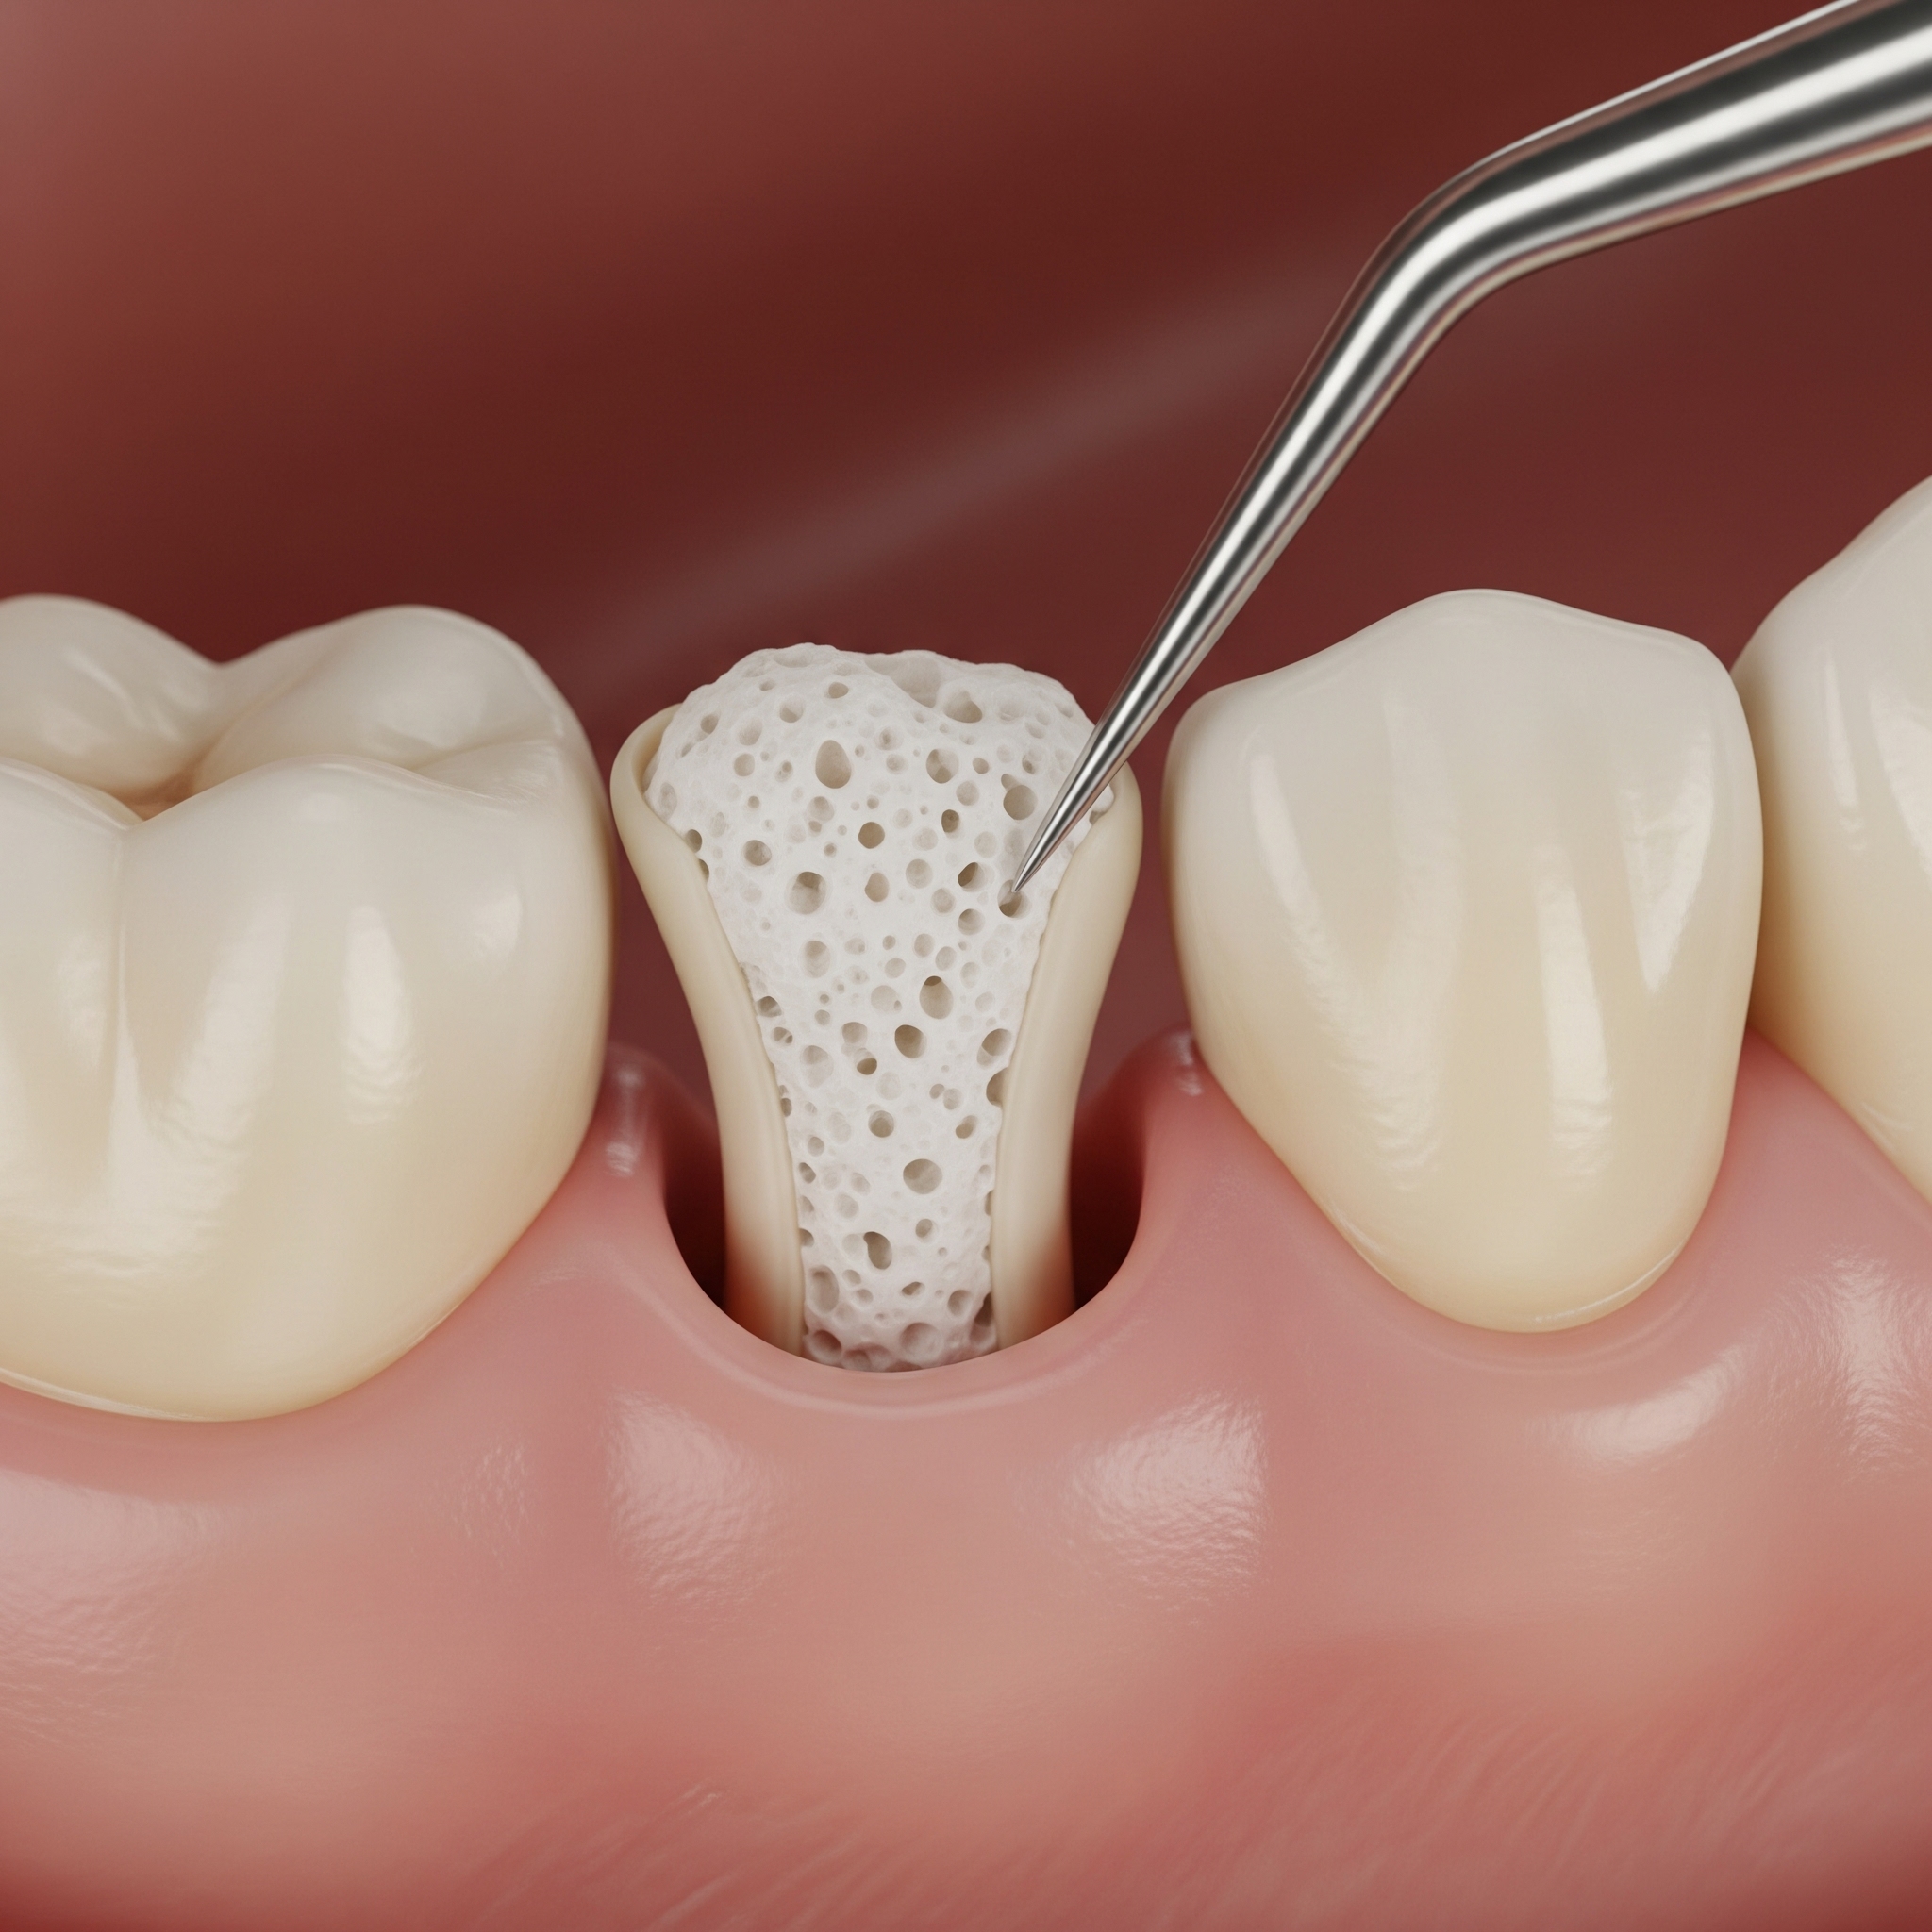

Apicoectomy

An apicoectomy is a minor oral surgical procedure used to treat persistent infections or inflammation at the tip of a tooth’s root, especially when a root canal alone isn’t sufficient. It helps preserve the natural tooth by removing infected tissue and sealing the root end.

- Precise removal of infected root tip and surrounding tissue

- Microsurgical techniques for minimal discomfort and fast healing

- Use of biocompatible materials to seal the root end

- Digital imaging to ensure accurate diagnosis and treatment

- Post-surgical care and monitoring for long-term success